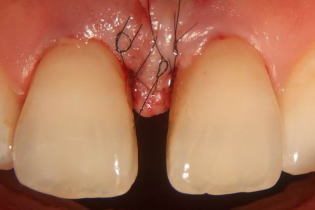

顕微鏡下で歯ぐきの外科処置を行い歯ぐきの治癒を妨げないよう髪の毛より細い縫合糸(7-0ナイロン)にて縫合した後の写真です。肉眼では取扱いの困難なほど細い糸なので歯ぐきも綺麗に治癒してきます。

| 施術の説明 | 顕微鏡を用いた歯ぐきの外科処置になります。歯ぐきの下の感染物質をきれいにしたあとに7−0ナイロン糸という極細の縫合糸を用いて歯ぐきの縫合をしています。 |

| 施術のリスク、副作用等 | 歯周外科処置のリスクは通常術後の歯ぐきの腫れ、出血、疼痛等を多少なりとも伴う処置になりますので抗生物質と鎮痛剤の服用を今回は1日しております。ただし顕微鏡下の処置によりそれらを最小限に抑えるように低侵襲で行っております。 |

| 施術の価格 | 55,000円 |